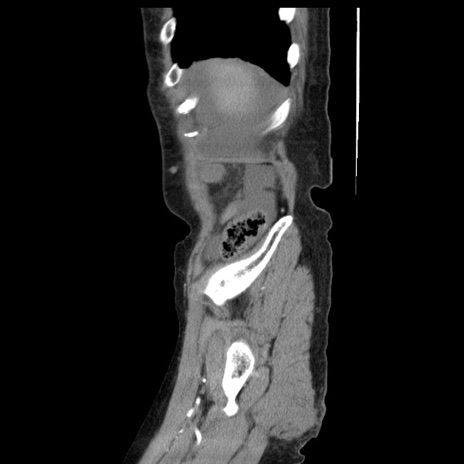

症例1(矢状断像)

【症例】80歳代女性

【主訴】腹痛

【現病歴】8時間前から腹痛あり来院。

【既往歴】糖尿病、脂質異常症、子宮体癌にて子宮全摘術

【身体所見】意識清明・会話良好だが腹痛で苦悶様、全腹部にわたって反跳痛と圧痛あり

【データ】WBC 13600、CRP 0.14、LDH 224、CK 90